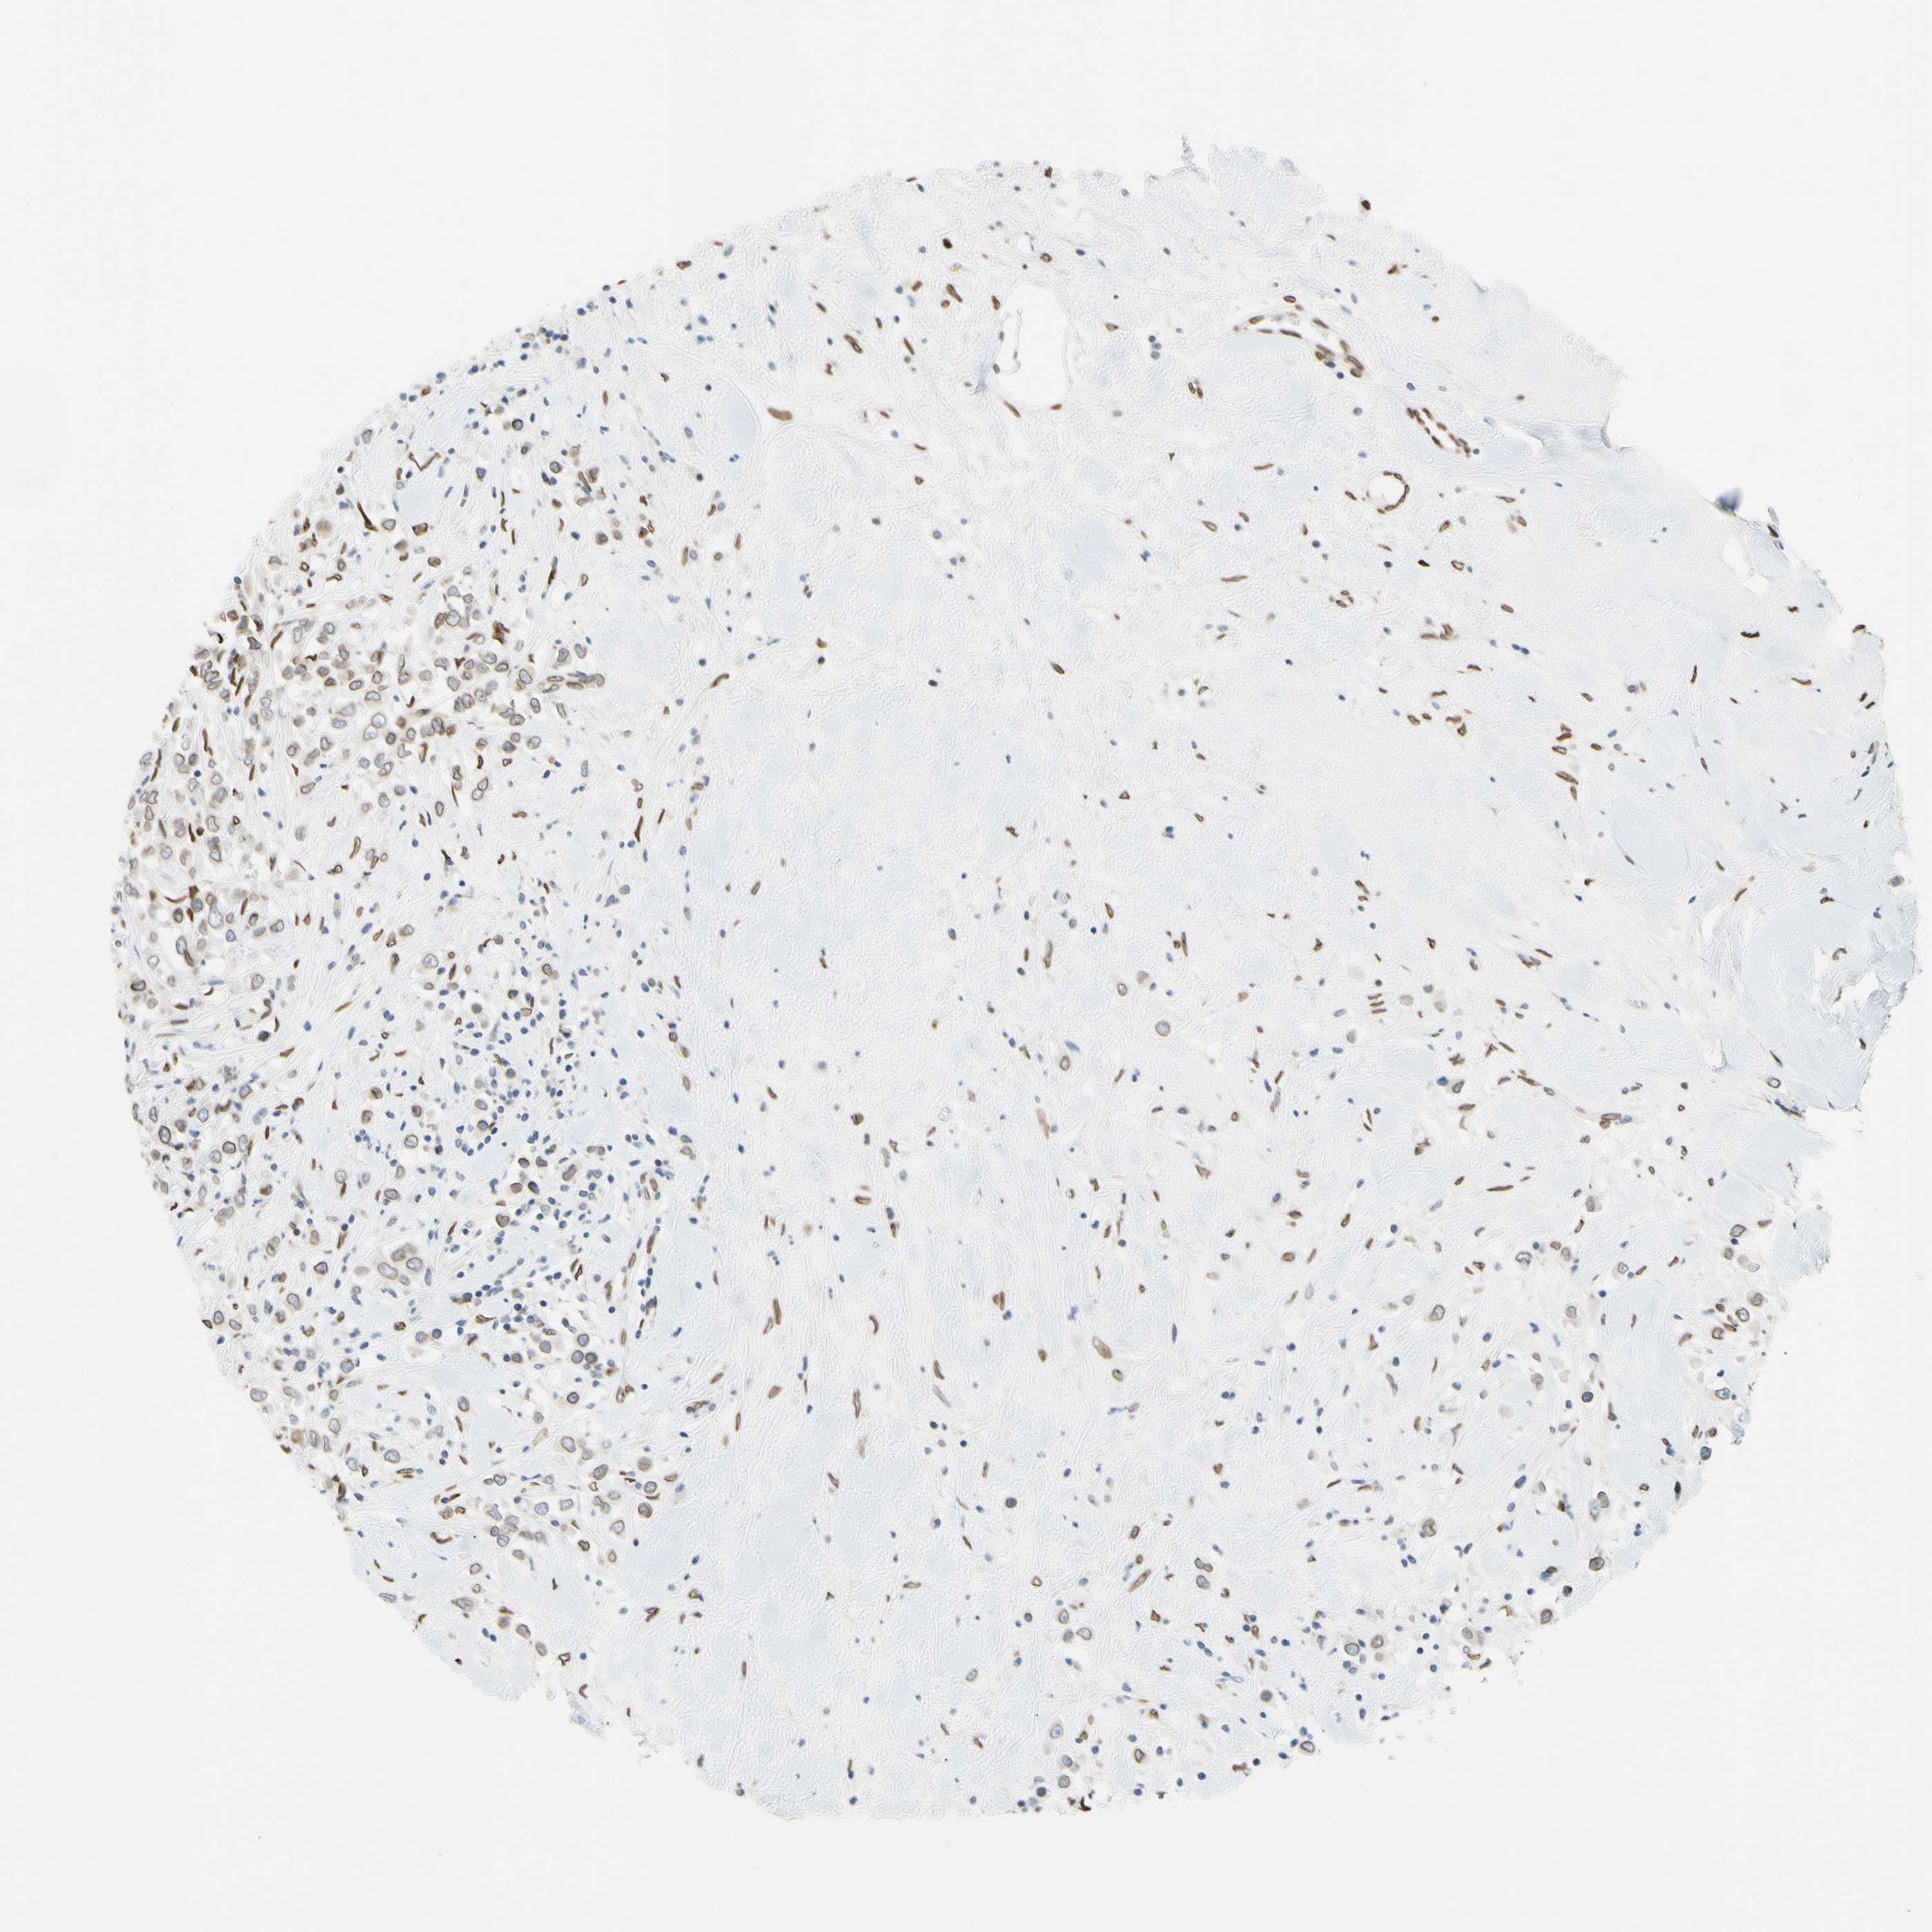

CANCER BREAST CANCER Show tissue menu

BRCA TCGA BRCA VALIDATION PROTEIN EXPRESSION